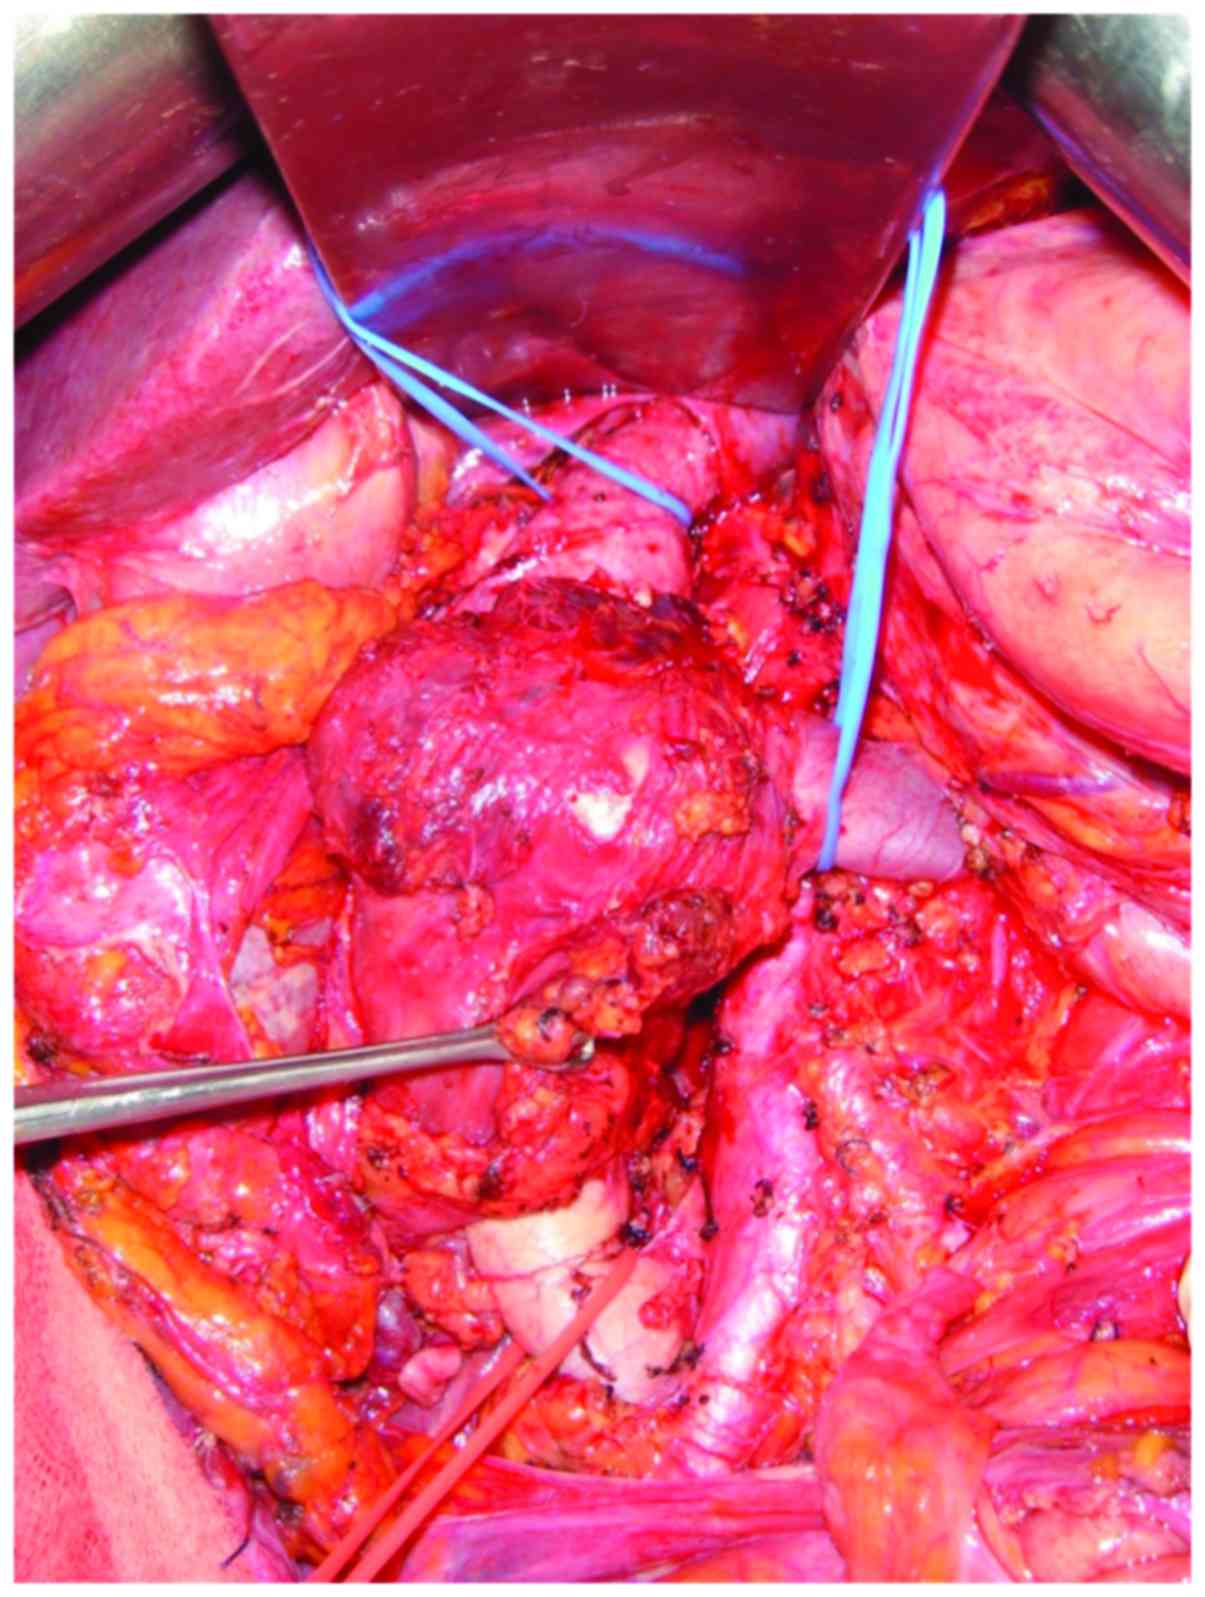

A 78-year-old male with a 4-month history of abdominal pain was admitted to the pancreas and biliary tract surgery service at the Clinics Hospital affiliated to the University of São Paulo (São Paulo, Brazil). A computed tomography (CT) scan (Fig. 2) of the abdomen revealed a 7.0 cm mass between the IVC and duodenum, which was suspected as a primary IVC tumor. The patient was referred to the surgical oncology group at the São Paulo Cancer Institute (São Paulo, Brazil) for further evaluation. The vascular surgery and surgical oncology teams planned the operative resection together. Exploration was performed via a midline incision. The mass was identified arising from the IVC and involved the lower and middle segment, and the right renal vein. Proximal and distal controls from the IVC were obtained (Fig. 3), and the mass and the right kidney were dissected free. The tumor was excised en bloc with 9.5 cm of the IVC and the right kidney with a 10 mm margin. IVC reconstruction was performed using an 18-mm Dacron prosthetic graft. Left renal vein reconstruction using a polytetrafluoroethylene (PTFE) prosthetic graft was performed (Fig. 4). The patient was heparinized. While on systemic anticoagulation, the patient was submitted to reoperation due to a postoperative retroperitoneal hematoma. The hematoma was evacuated and no active bleeding was identified. The patient was discharged home on warfarin. Surgical pathological examination demonstrated a multilobulated high-grade 8.0 cm LMS of the IVC with negative surgical margins. The patient remained well for 28 months; however, multiple pulmonary nodules were identified in the routine surveillance CT scan. The patient subsequently underwent multiple metastasectomies with subsequent recurrences. The patient succumbed to the disease 57 months following the original resection.

![]() | Figure 3.Retroperitoneal tumor dissected in a patient with leiomyosarcoma of the inferior vena cava. |